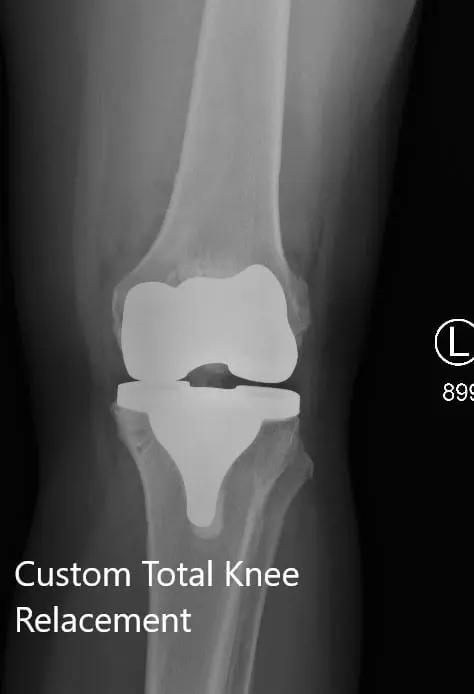

Postoperative X-ray showing the AP and lateral views of the left knee

Postoperative X-ray showing the AP and lateral views of the left knee - img 2

Postoperative X-ray showing the AP and lateral views of the left knee.